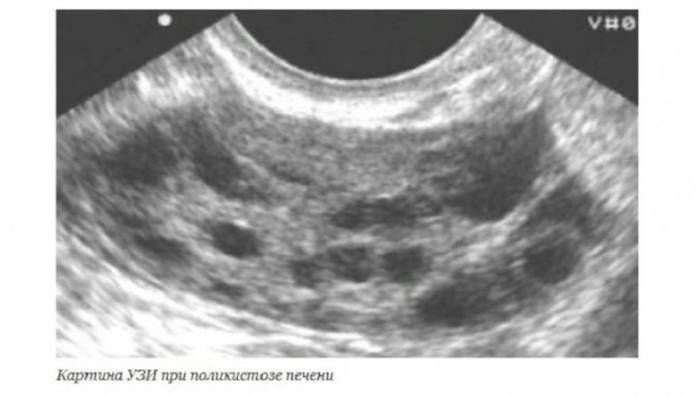

УЗИ является достоверным и доступным методом обследования. Но нужно помнить, что киста левой доли печени на УЗИ плохо визуализируется.

При ультразвуковой диагностике можно увидеть такую картину (см. фото ниже).